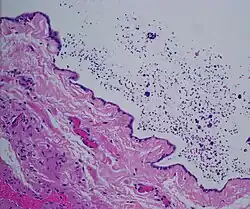

Micrograph of a spermatocele. The characteristic sperm are present (black dots - left of image). H&E stain.

Dilated rete testis containing spermatozoa within cyst lumen. H&E stain 20x